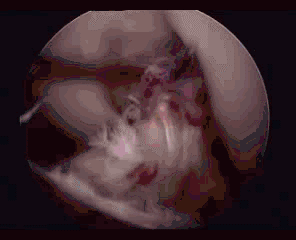

11.半月板桶柄状撕裂:为膝关节的一种严重损伤,常伴有ACL损伤。

24.jpg